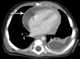

Amebic lung abscess with rupture into pericardial sac

Constrictive pericarditis